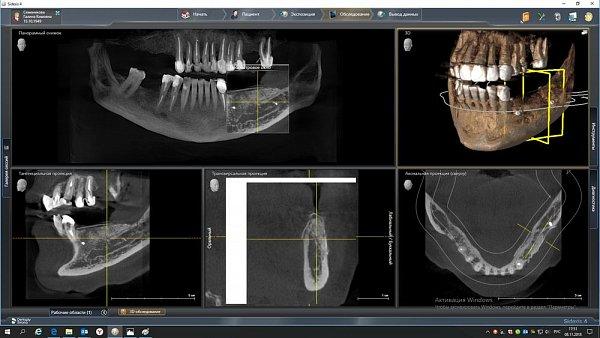

Пациент обратился с целью протезирования. На компьютерной томографии выявлен недостаток костной ткани по высоте (3−5 мм) за счет углубления гайморовой пазухи. Следующим этапом в области отсутствующих зубов 1.5, 1.6 и 1.7 планируется дентальная имплантация.

Врачом А.Г. Геворкяном выполнена операция по наращиванию костной ткани (открытый синуслифтинг). На контрольном снимке определяется увеличение объема костной ткани по высоте.